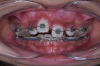

Fig 7. Clinical situation after rapid palatal expansion and orthodontic traction, frontal view (Fig 7) and occlusal view (Fig 8).

Fig 8. Clinical situation after rapid palatal expansion and orthodontic traction, frontal view (Fig 7) and occlusal view (Fig 8).